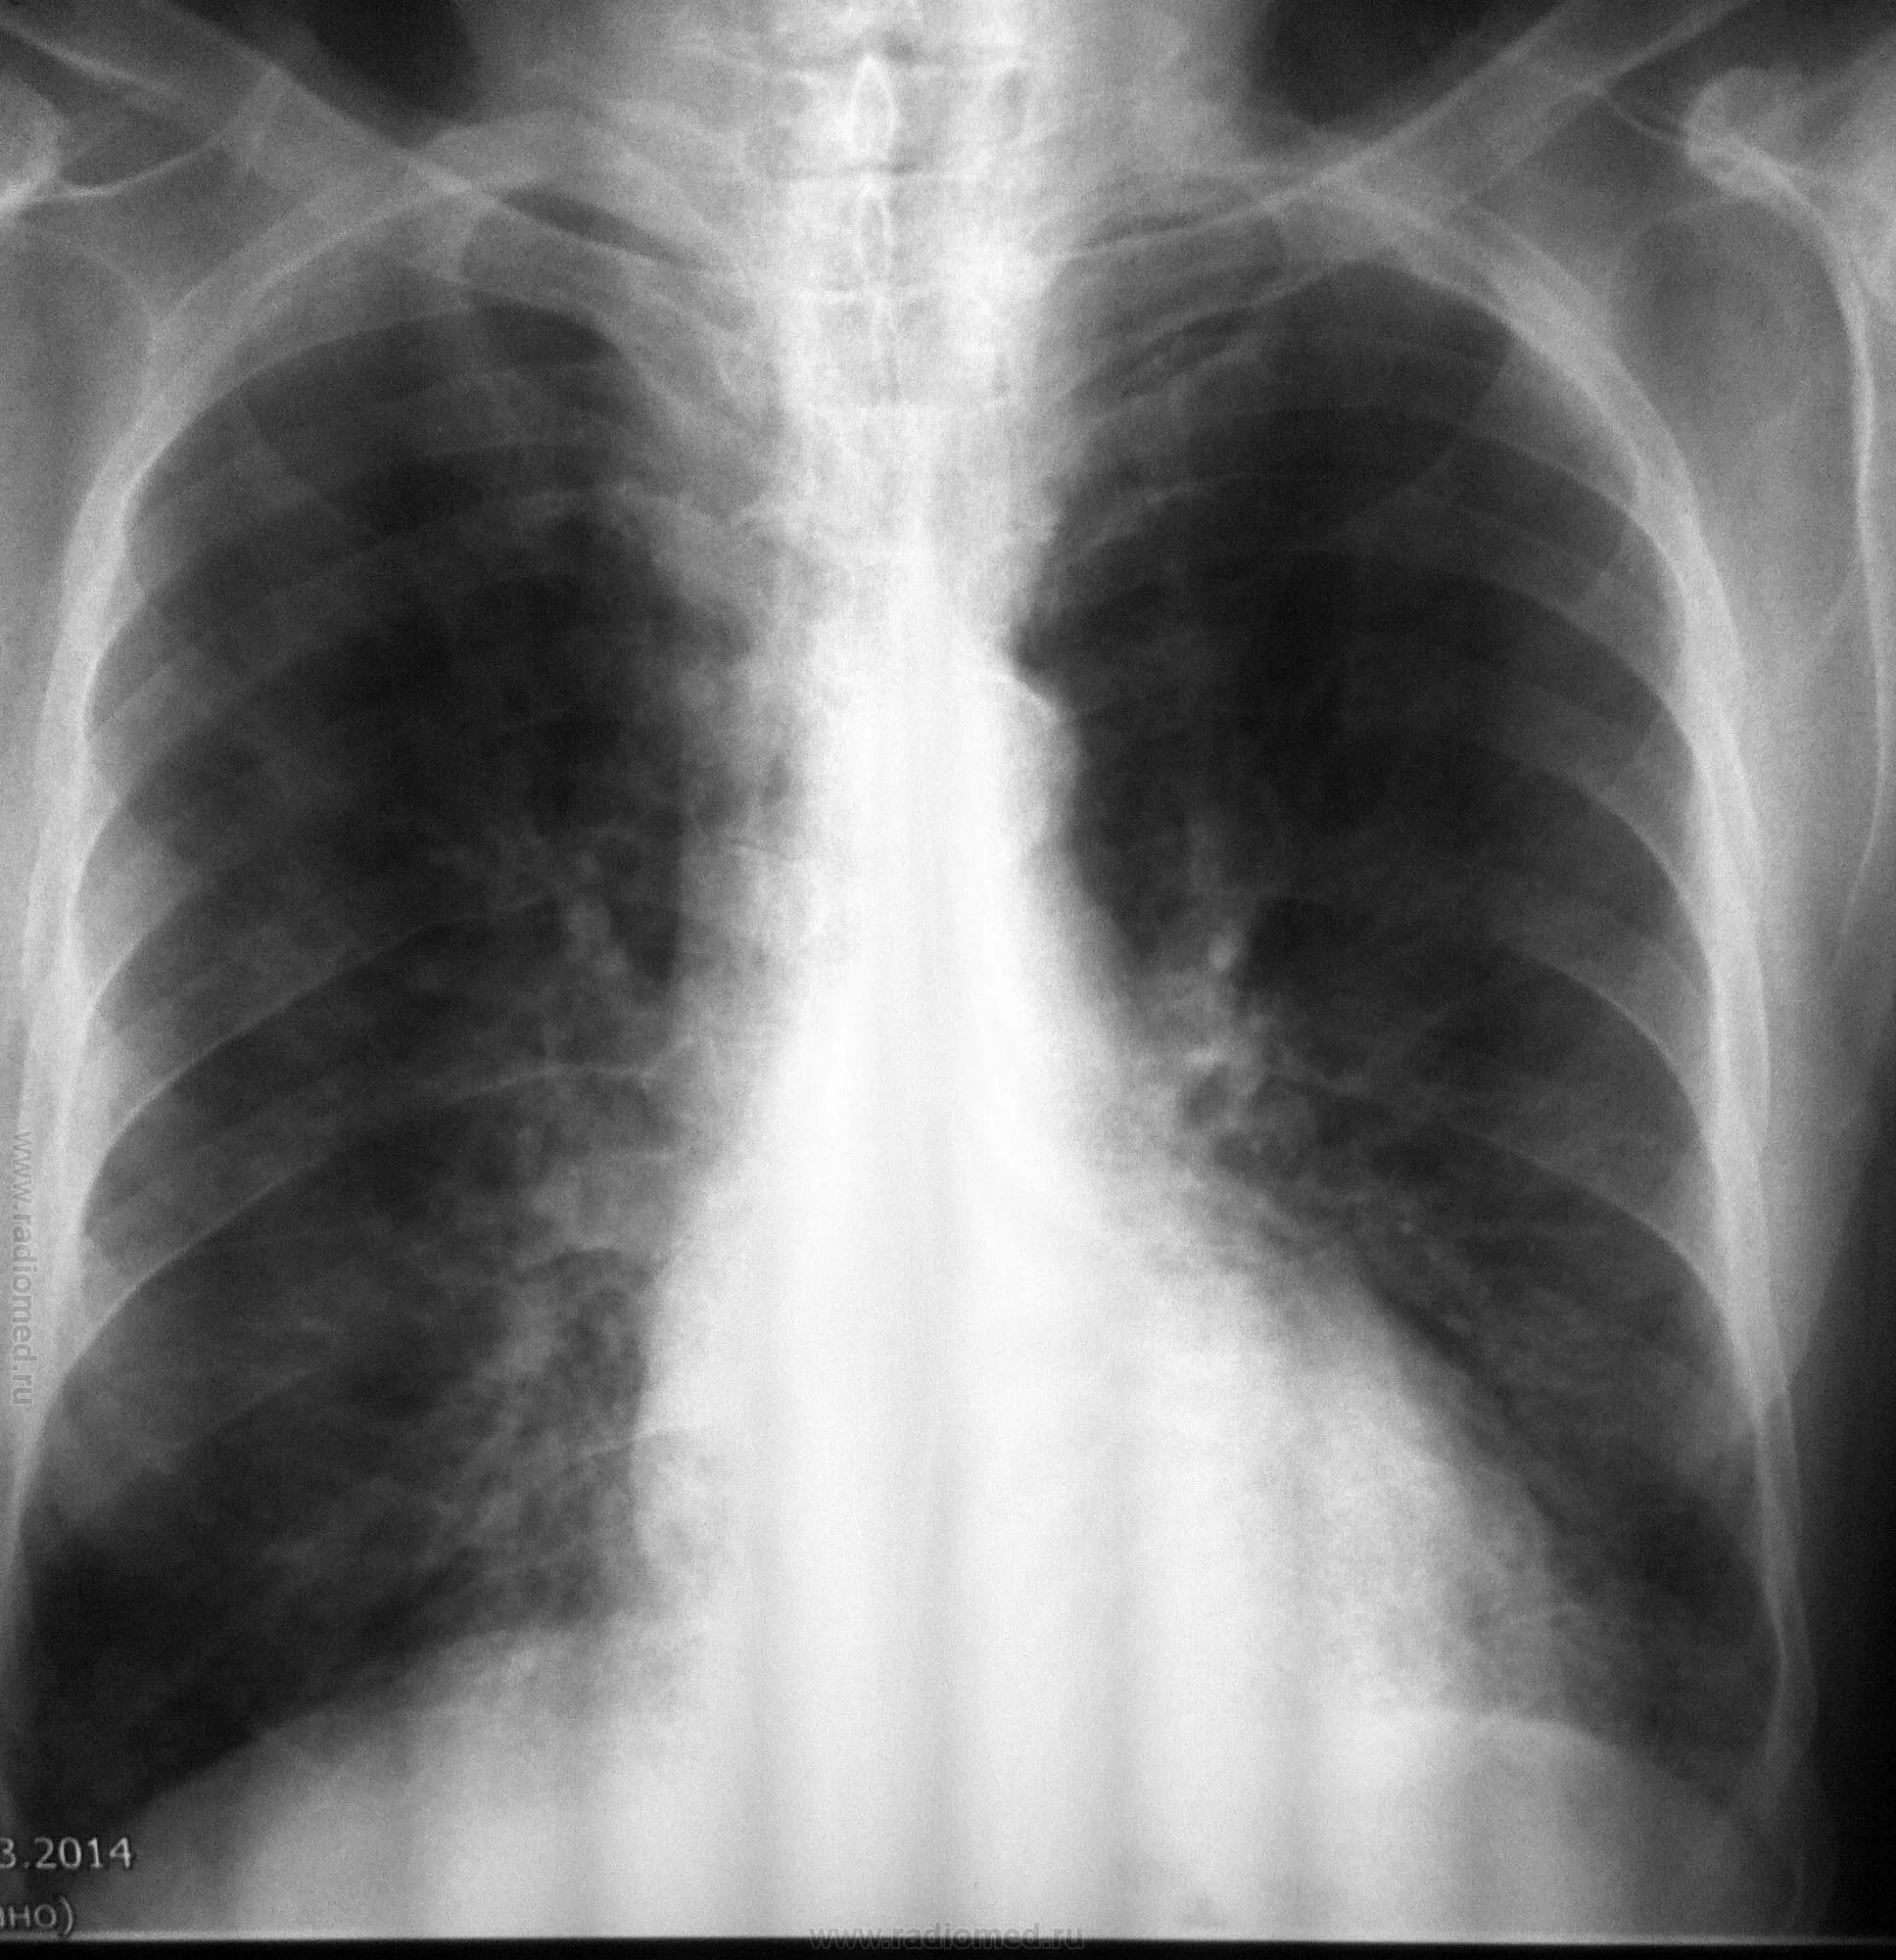

Диффузный эндобронхит